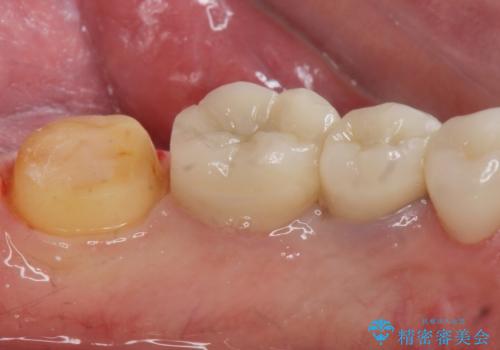

- 過去に治療したゴールドの詰め物が取れて来院。取れたのは2回目だそうです。レントゲンでは適合が良いので再装着可能だったが、

もう取れたくないとの事だったので被せ物のご案内をしました。ゴールドの被せ物の希望だったのでゴールドクラウンでの治療になりました。

適合の良いゴールドクラウンが入りました。

ゴールドは適合が良く、割れる心配もありません。

また、虫歯になるリスクも銀歯と比べて低くなります。